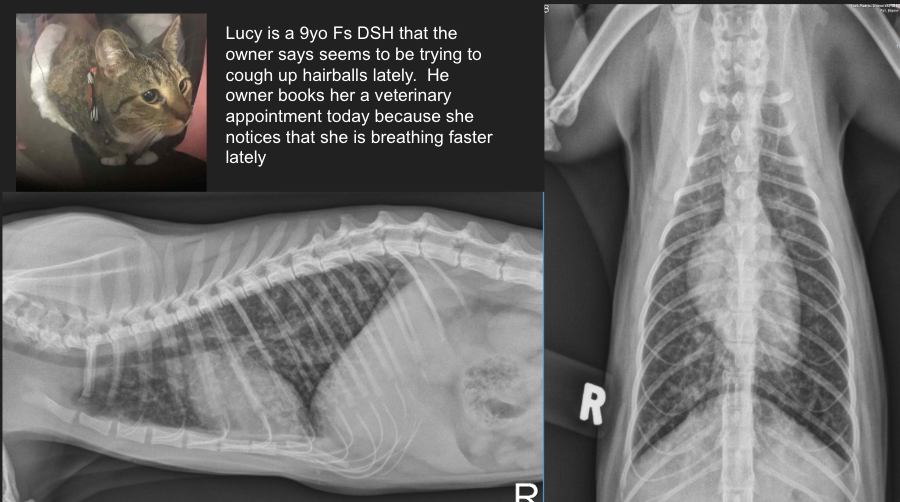

Lucy is a 9yo Fs DSH that the owner says seems to be trying to cough up hairballs lately. He owner books her a veterinary appointment today because she notices that she is breathing faster lately.

Lung pattern?

ddx?

Diffuse bronchial pulmonary pattern (donuts and tram tracks)

ddx: feline asthma